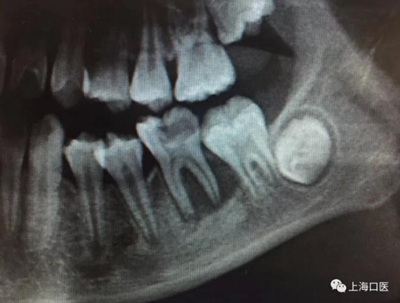

這是上海武廣增正畸工作室接診的一例非常規(guī)拔牙矯治病例,患者女性,初診年齡14歲。LL6殘冠拔除。LL7近中平移取代LL6,我們上傳了該患者一組下頜磨牙近中平移連續(xù)矯治過程的正畸X線片,與正畸界朋友分享。

來源:武廣增 上海口醫(yī)